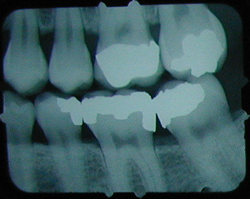

No cavity on first X-ray.

|

Months later, cavities that start

between the teeth can't be seen by visual examination,

but they can be detected on an X-ray.

|

This cavity was detected and filled before the patient felt any discomfort, and before the nerve became infected or the tooth became abscessed.

There is another cavity shown in the X-ray on the right. Can you find it? It's difficult for the untrained eye to spot. Click here to see where it is. (Hint: It's not the left edge of the top left tooth. That's just the edge of the frame around the X-ray).